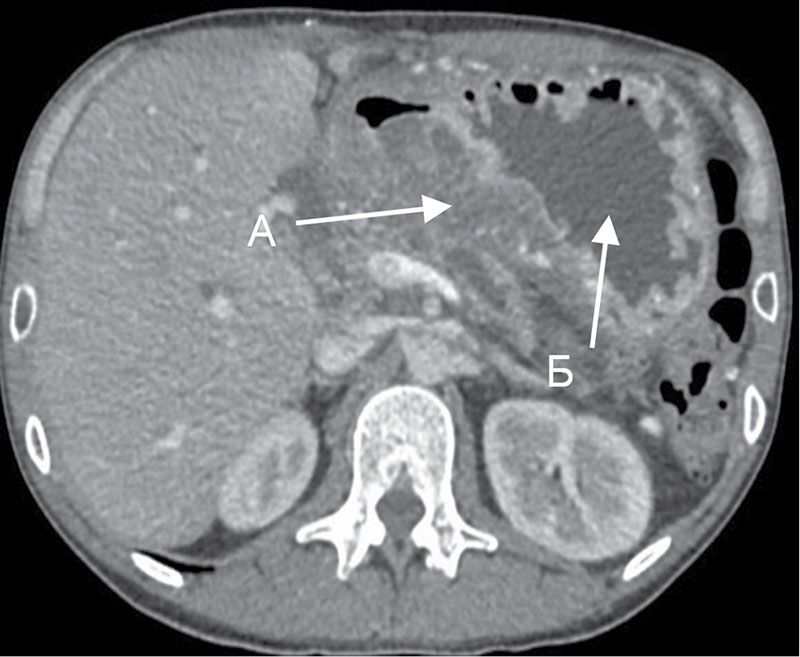

УЗИ диагностика кольцевидной поджелудочной железы: что важно знать